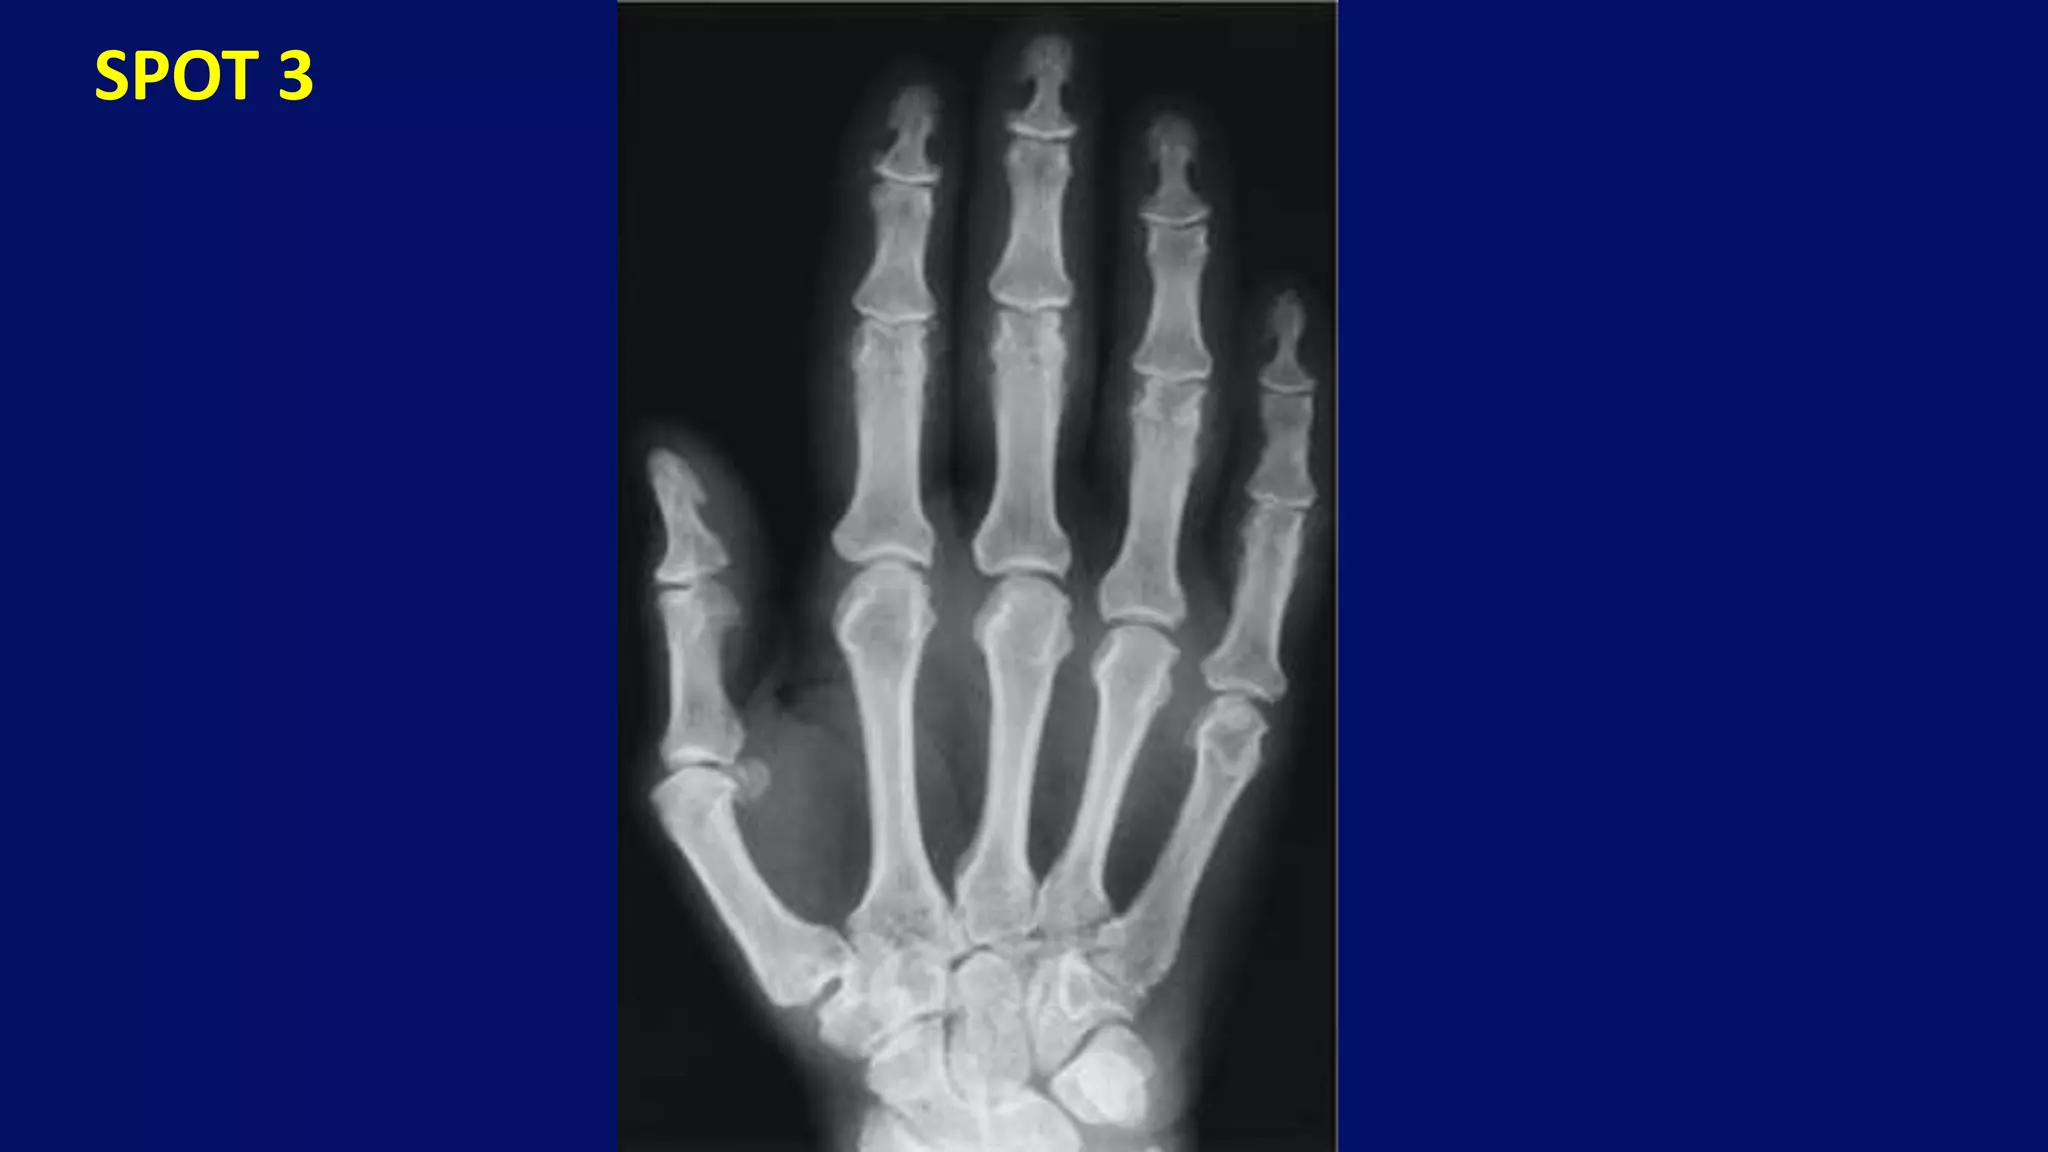

SPOT 3

• #136 20 years old male with hand pains and swellings. Note acrosteolysis and globular soft tissue calcifications characteristic of progressive systemic sclerosis.